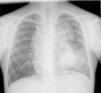

Se realizó una radiografía de tórax que mostraba ensanchamiento mediastínico anterosuperior y medio junto con masa pulmonar adyacente en el lóbulo inferior izquierdo (fig. 1). En la serie ósea presentaba reacción perióstica en el primer metacarpiano y cúbito que afectaba a toda la longitud del hueso y focal en las diáfisis tibial, peronea y del primer metatarsiano, imágenes indicativas de osteoartropatía hipertrófica (OAH) (figs. 2 y 3).